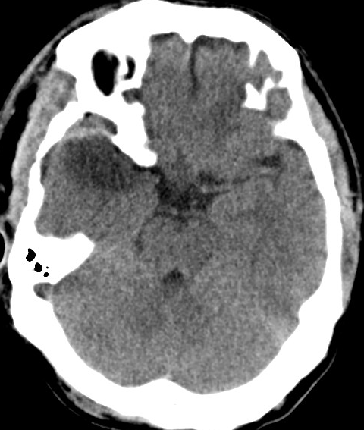

2014-9-29 CT

2014-10-5 CT